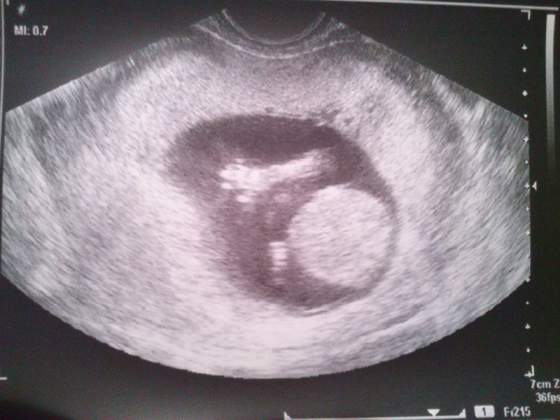

Wczoraj wyszłam z koleżanką na kawę, później przyszłyśmy do mnie bo mąż chciał pobiegać, a jak Nela spać poszła to oczywiście kłótnia... Dziś po jego pracy to samo. Kurcze mam już dość. W dodatku powiedziałam mu w końcu, co czuję odnośnie posiadania syna... To kazał mi do psychologa iść, wkurzył się potwornie. Dziś mamy niby jeszcze rozmawiać na ten temat, ale co ja poradzę że nie potrafię się cieszyć, że będziemy mieli syna? Nie miałam pojęcia, że moja niechęć do chłopców aż tak na mnie wpłynie... Wydaje mi się, że ja nigdy nie chciałam mieć syna ze względu na mojego ojca- zawsze widziałam w nim ucieleśnienie najgorszego wychowania, wiedziałam że dziadkowie zrobili z niego takiego człowieka, przez co ja od zawsze mam w głowie, że synowie są tacy do niczego...